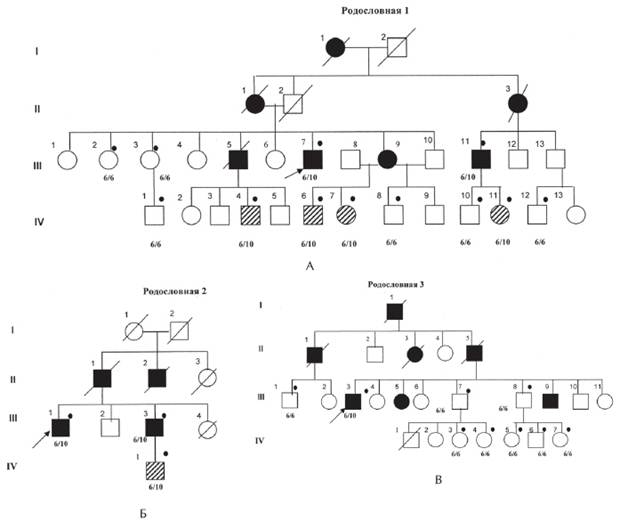

Рисунок 1. Рис. 1. А, Б, В. Родословные семей с офтальмоплегической мышечной дистрофии Кило-Невина с результатами ДНК-диагностики [Codere F., Brais B., Rouleau G., Lafontaine E., 2001].

Примечание. 6/6; 6/10 тАФ результаты ДНК-анализа на мутацию в гене PABPN1; Закрашенный кружок тАФобследованные пациенты; закрашенный квадрат тАФ больной с ОФМД, пустой квадрат тАФ клинически здоровый; заштрихованный квадрат тАФ клинически здоровый носитель мутации в гене PABPN1. I, II поколение тАФ умершие родители, III поколение тАФ больные и их сибсы, IV тАФ дети, не достигшие возраста начала заболевания